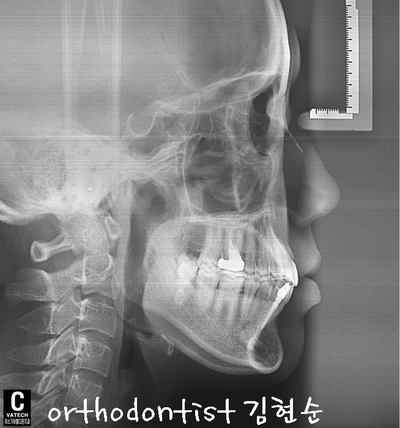

- 교정 후 개선된 치아 중심선입니다

- implant 식립 후 개선된 치열 옆모습입니다

- 상 / 하 모두 교정 후 가지런한 모습으로 마무리되었습니다

-

처음보다 달라진 이미지가 보여지며 밝은 미소 또한 갖게 되었습니다

이 모습 오래오래 간직하세요 ^^